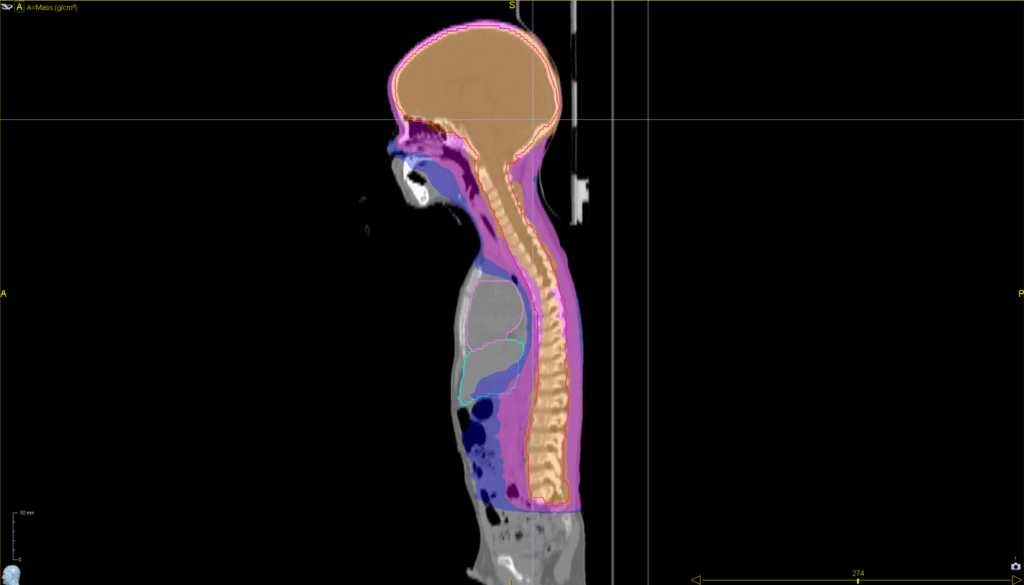

Treatment Plan Images

ClearRT® Images